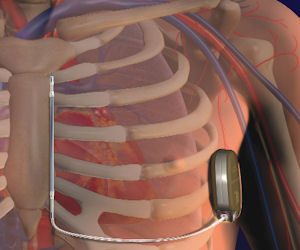

Cameron, which has raised some $85 million in funding, makes a defibrillator that’s implanted under the skin and provides an electric shock to interrupt a potentially fatal heart rhythm during a heart attack.

The device differs from others in that it operates without electrical lead wires within a patient’s veins. Instead, it directly links to the heart, lessening the risk of fractures and scar tissue buildup.

Problems with electrical lead wires have led to complications, regulatory recalls and bad publicity—something analysts contend have blemished the sector’s growth and progress.